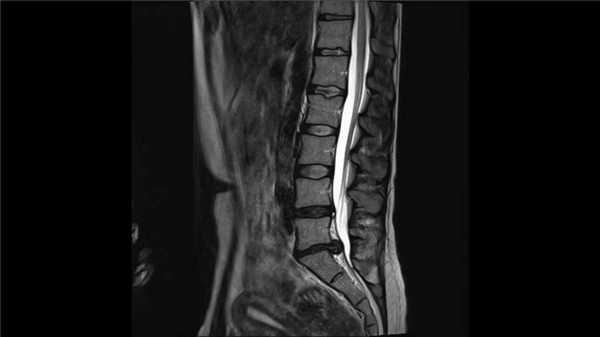

Б. При МРТ в режиме STIR также виден перелом позвонка без признаков повреждения заднего связочного комплекса.

Обратите также внимание на наличие очага контузии в конусе спинного мозга.